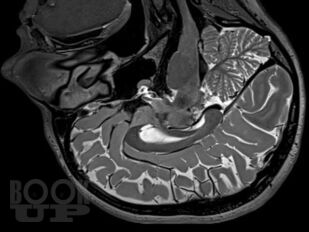

В руководстве представлены сведения о редко встречающихся (в том числе орфанных) неврологических синдромах и болезнях, сгруппированных в 4 главы в зависимости от этиологии: аутоиммунные и воспалительные; врожденные пороки развития нервной системы, наследственные и дисметаболические; опухоли нервной системы и паранеопластические синдромы; нейродегенеративные заболевания. В отношении каждой болезни представлены эпонимические сведения, шифр по МКБ-10, эпидемиология, этиология, патогенез, патоморфология, клиническая картина, диагностика, дифференциальная диагностика, лечение и прогноз. Все разделы книги иллюстрированы собственными клиническими случаями и результатами их обследований.